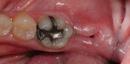

Diş ekimi, günümüzde oldukça yaygın bir işlem olmasına rağmen, her cerrahi müdahalede olduğu gibi bazı riskleri de beraberinde getirebilir. Enfeksiyon ve vücut reddi, bu işlemin potansiyel komplikasyonları arasında yer alır. Ancak, bu riskler uygun önlemlerle önemli ölçüde azaltılabilir.

1. Uzman Seçimi: Diş ekimi yapacak olan doktorun deneyimi ve uzmanlığı, işlemin güvenliği açısından kritik öneme sahiptir. Güvenilir bir hekim seçmek, komplikasyon riskini azaltır.

2. Steril Ortam: İşlem sırasında kullanılan aletlerin ve ortamın steril olmasına dikkat edilmelidir.

3. Hastanın Genel Sağlık Durumu: İşlem öncesi genel sağlık kontrolü yapmak, mevcut sağlık sorunlarının tespit edilmesine ve buna göre önlem alınmasına yardımcı olur.

4. İlaç Kullanımı: Doktorun önerdiği antibiyotik ve ağrı kesicilerin düzenli kullanımı enfeksiyon riskini azaltabilir.